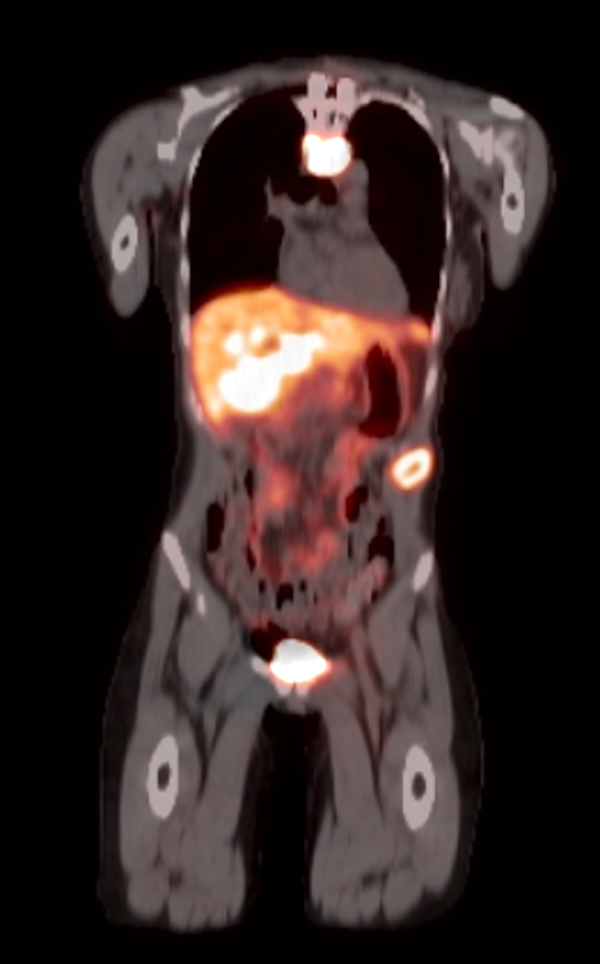

Radiology description

- Anatomical imaging studies: Doppler ultrasonography, CT, MRI, MRA, CT angiography (Cancer Imaging 2012;12:153, Insights Imaging 2019;10:29, Eur J Nucl Med Mol Imaging 2019;46:2112)

- Functional imaging studies: there are 3 types of PET / CT radiopharmaceuticals that exert their actions through different receptors: 18F-FDG, 18F-fluorodopa (18F-FDOPA) and 68Galium(68Ga)-tetraazacyclododecanetetraacetic acid (DOTA) analogs (Front Endocrinol (Lausanne) 2018;9:515)

- Ga 68-DOTATATE PET / CT is the preferred modality, binds to somatostatin receptor (SSTR2) expressed in paragangliomas with a detection rate of 80 - 100%, demonstrating increased uptake in the tumor anatomical location

- See Radiology images